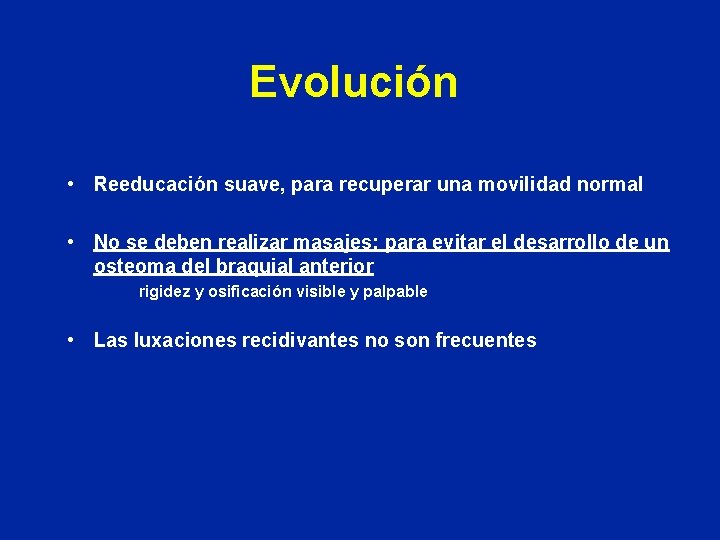

Evolución • Reeducación suave, para recuperar una movilidad normal • No se deben realizar masajes: para evitar el desarrollo de un osteoma del braquial anterior rigidez y osificación visible y palpable • Las luxaciones recidivantes no son frecuentes